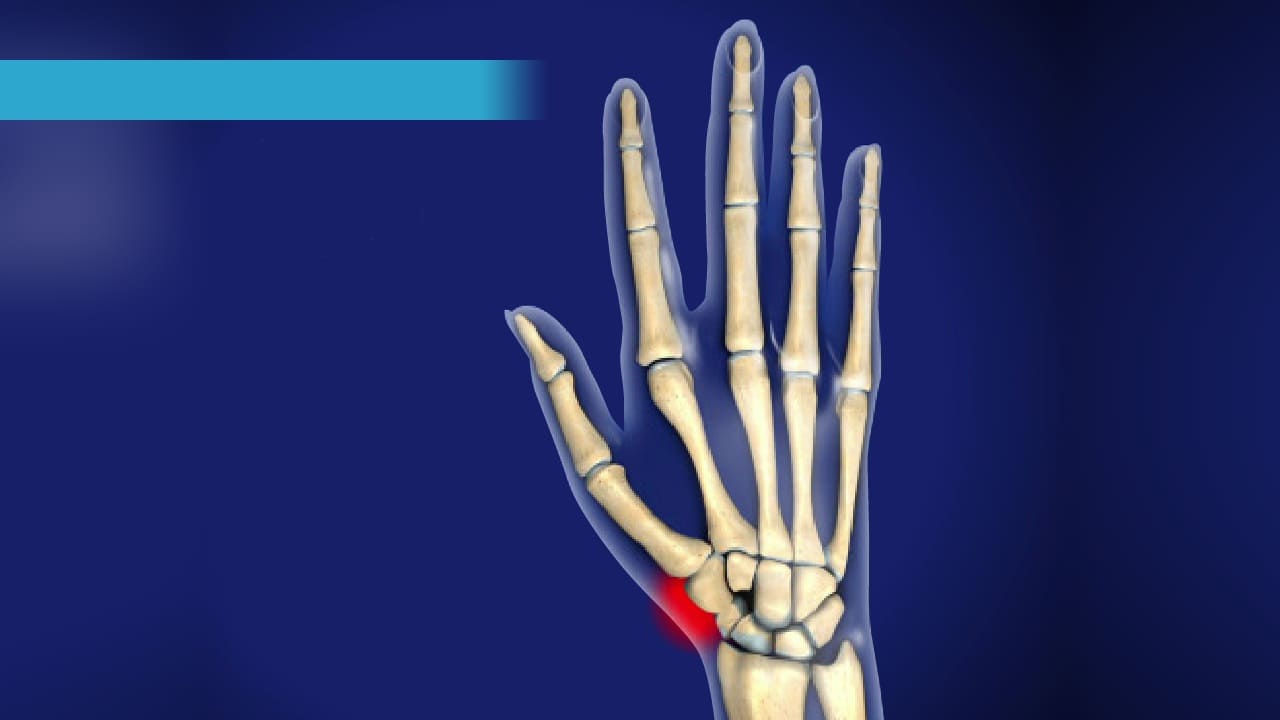

Thumb Pain – 1st CMC Arthritis